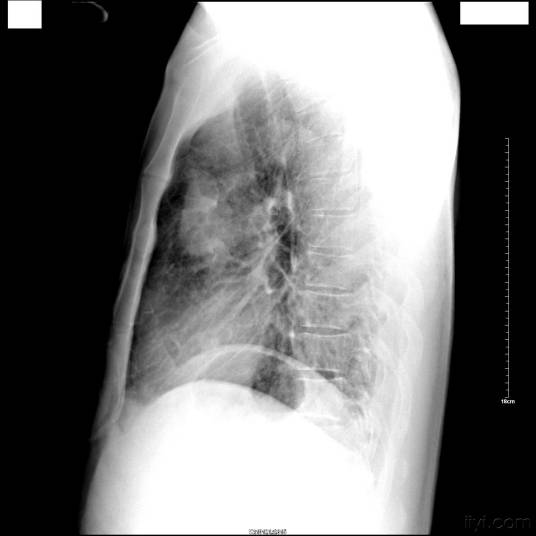

占位性病变是医学影像诊断学中的专用名词,通常出现在X射线、B超、CT等检查结果中。是指被检查的部位里有一个“多出来的东西”,这个“多出来的东西”可使周围组织受压、移位。占位性病变通常泛指肿瘤(良性的、恶性的)、寄生虫等,而不涉及疾病的病因。

良性占位性病变从大体上可分为囊性占位和实质性占位两种类型,囊性占位性病变主要包括囊肿、脓肿等,其中囊肿较常见;实质性占位主要包括血管瘤、细胞腺瘤、局灶性结节性增生、局灶性脂肪肝、炎性假瘤、瘤样增生等,其中以血管瘤最为常见。发现有占位病变后,首先要定性论断,即确定病人占位的性质,是良性还是恶性。各种影像学检查不但可以配合定性论断,还可以进行定位论断,也就是进一步确定占位病变的位置、大小、数目及其与周围组织的关系,定位诊断最常用的是CT、核磁共振扫描成像、B超,必要时可应用动脉血管造影,为能否手术治疗提供依据。